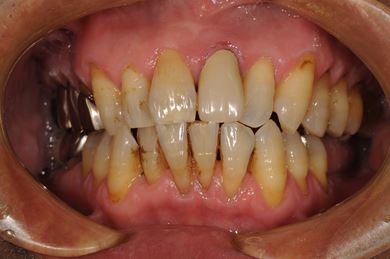

| 性別/年齢 | 男性 / 60歳 | ||||||||||||||||||||||||||||||||

| 主訴 | 右下奥歯の治療相談。(痛み・ぐらつき・物がかめない) | ||||||||||||||||||||||||||||||||

| 治療方針 | 左下奥の欠損部分をインプラント治療にて、機能的・審美的に回復を行う。 | ||||||||||||||||||||||||||||||||

| 治療内容 | インプラント2本、メタルボンドセラミッククラウン2本 | ||||||||||||||||||||||||||||||||

| 総治療費 | 680,610円 | ||||||||||||||||||||||||||||||||

| 治療期間 | 7ヶ月 |